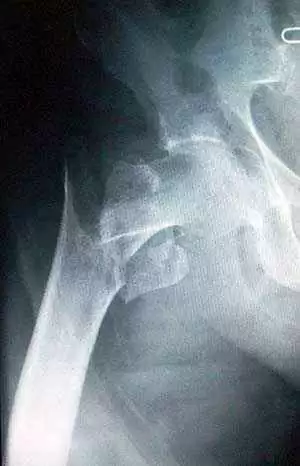

Results did show that persistent villous atrophy was connected with an increased risk of hip fracture (HR 1.67, 95% CI 1.05–2.66). The risk of hip fracture rose in relation to the degree of villous atrophy; the more villous atrophy, the higher the risk of hip fracture.

Overall, HR for partial villous atrophy compared with those with healing was 1.70, with a 95% CI 0.82–3.49 (HR for subtotal/total villous atrophy compared with those with healing 2.16, 95% CI 1.06–4.41).

The results indicate that persistent villous atrophy on follow-up biopsy can be used to predict the risk of hip fracture in patients with celiac disease.